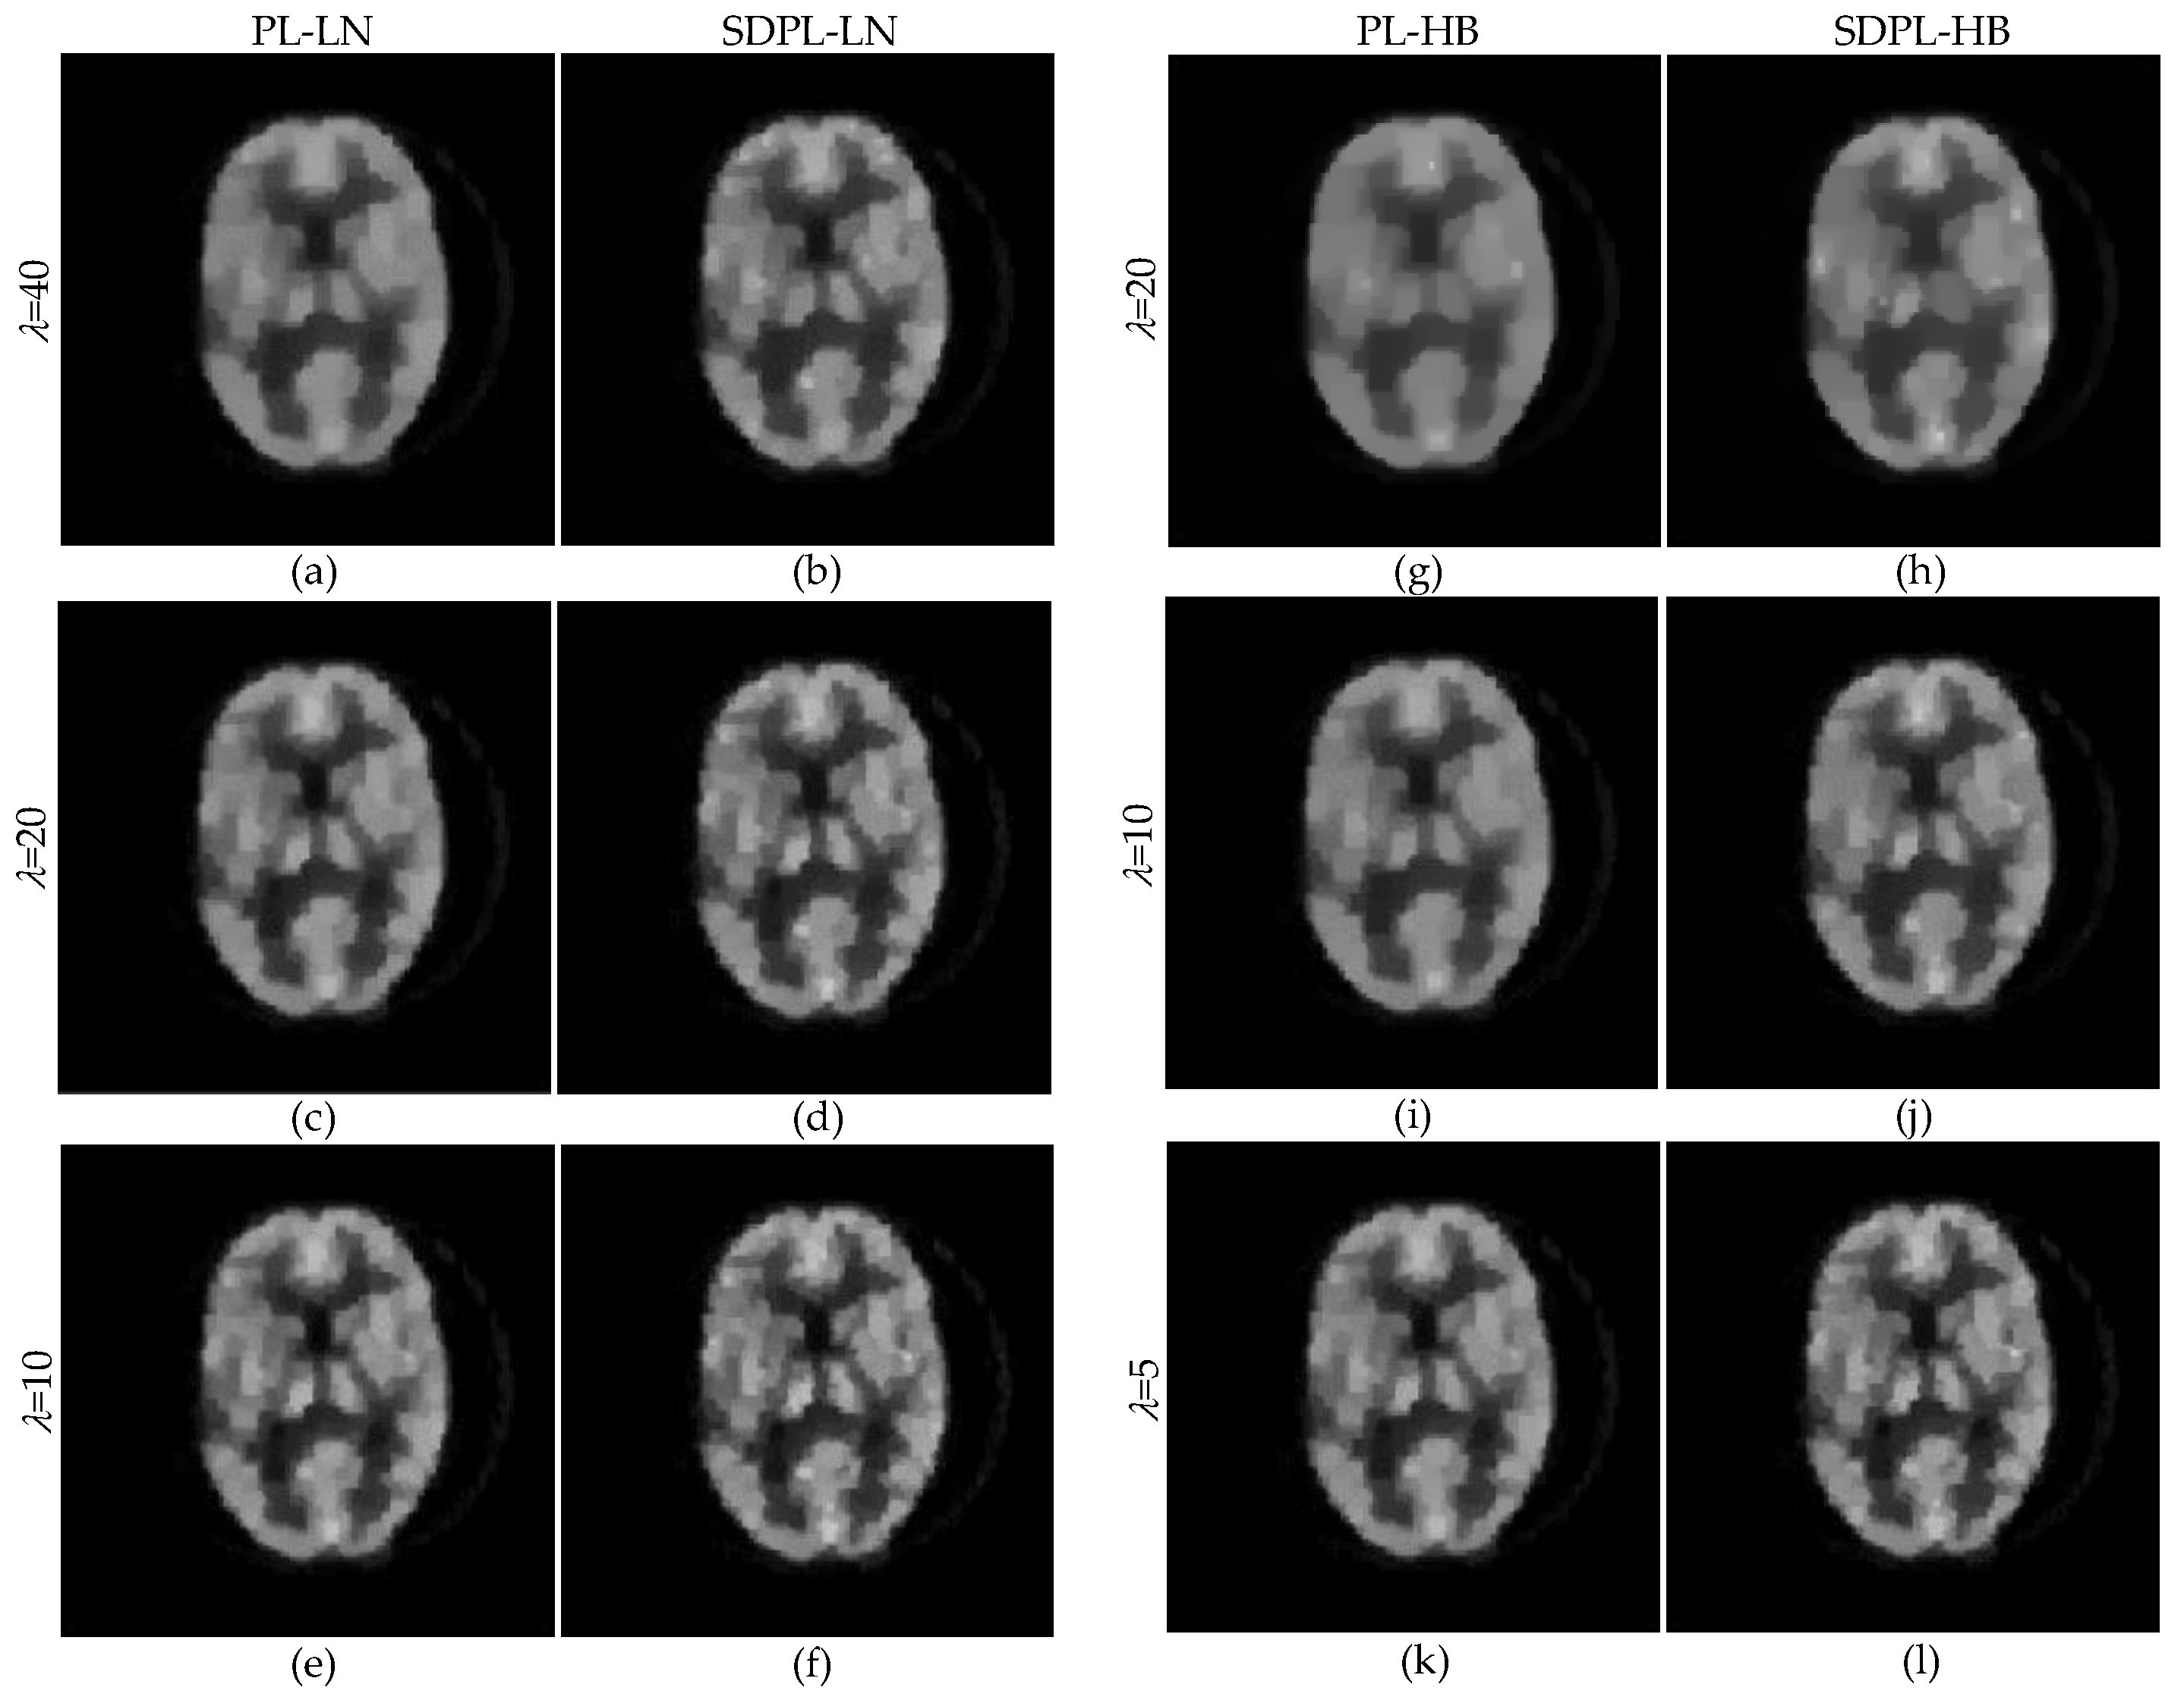

| IQA Metrics | PL-LN | SDPL-LN | |||

|---|---|---|---|---|---|

| GR | SD | PS | |||

| = 40 = 0.1 | PSNR(dB) | 13.943 | 15.569 | 15.621 | 14.999 |

| SSIM | 0.821 | 0.872 | 0.874 | 0.854 | |

| VIF | 0.404 | 0.540 | 0.547 | 0.531 | |

| MAE | 0.090 | 0.068 | 0.068 | 0.071 | |

| RMSE | 0.201 | 0.167 | 0.166 | 0.178 | |

| MPE | 36.651 | 30.396 | 30.216 | 32.459 | |

| = 40 = 0.03 | PSNR(dB) | 15.475 | 17.133 | 17.232 | 16.856 |

| SSIM | 0.869 | 0.910 | 0.912 | 0.905 | |

| VIF | 0.539 | 0.675 | 0.688 | 0.672 | |

| MAE | 0.069 | 0.051 | 0.050 | 0.052 | |

| RMSE | 0.168 | 0.139 | 0.138 | 0.144 | |

| MPE | 30.728 | 25.387 | 25.101 | 26.210 | |

| = 20 = 0.15 | PSNR(dB) | 14.659 | 16.186 | 16.222 | 15.756 |

| SSIM | 0.843 | 0.887 | 0.887 | 0.876 | |

| VIF | 0.474 | 0.593 | 0.598 | 0.590 | |

| MAE | 0.079 | 0.061 | 0.061 | 0.063 | |

| RMSE | 0.185 | 0.155 | 0.155 | 0.163 | |

| MPE | 33.754 | 28.311 | 28.194 | 29.748 | |

| = 20 = 0.05 | PSNR(dB) | 16.001 | 17.543 | 17.601 | 17.151 |

| SSIM | 0.882 | 0.919 | 0.920 | 0.913 | |

| VIF | 0.587 | 0.720 | 0.730 | 0.706 | |

| MAE | 0.063 | 0.047 | 0.046 | 0.050 | |

| RMSE | 0.159 | 0.133 | 0.132 | 0.139 | |

| MPE | 28.922 | 24.217 | 24.056 | 25.335 | |